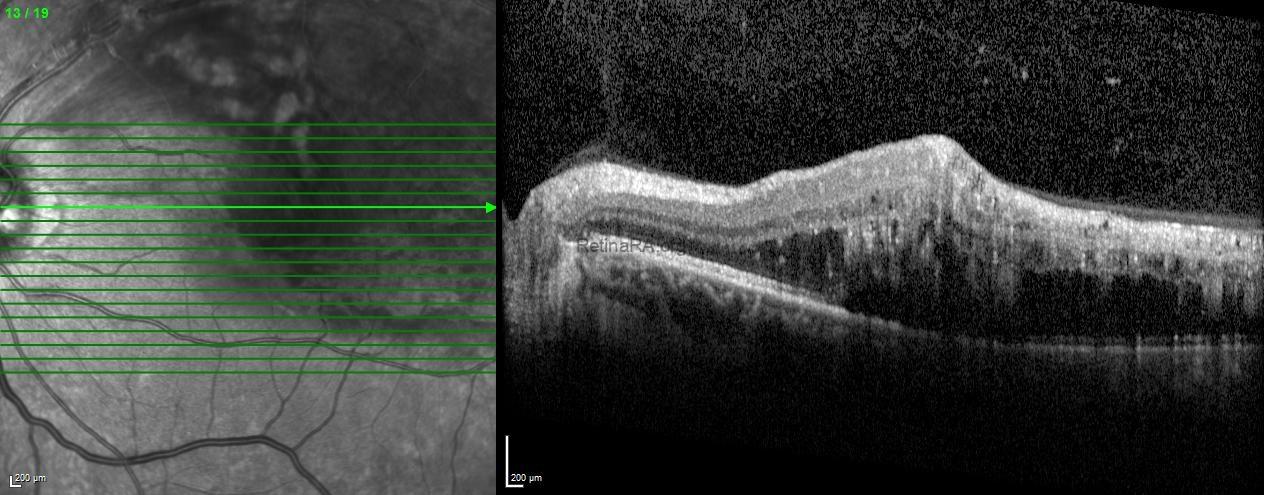

Spectral-domain optical coherence tomography of the left eye showed increased central macular thickness with intraretinal cystoid spaces and subretinal fluid. Hyperreflective foci with posterior shadowing, consistent with hard exudates, were also observed.